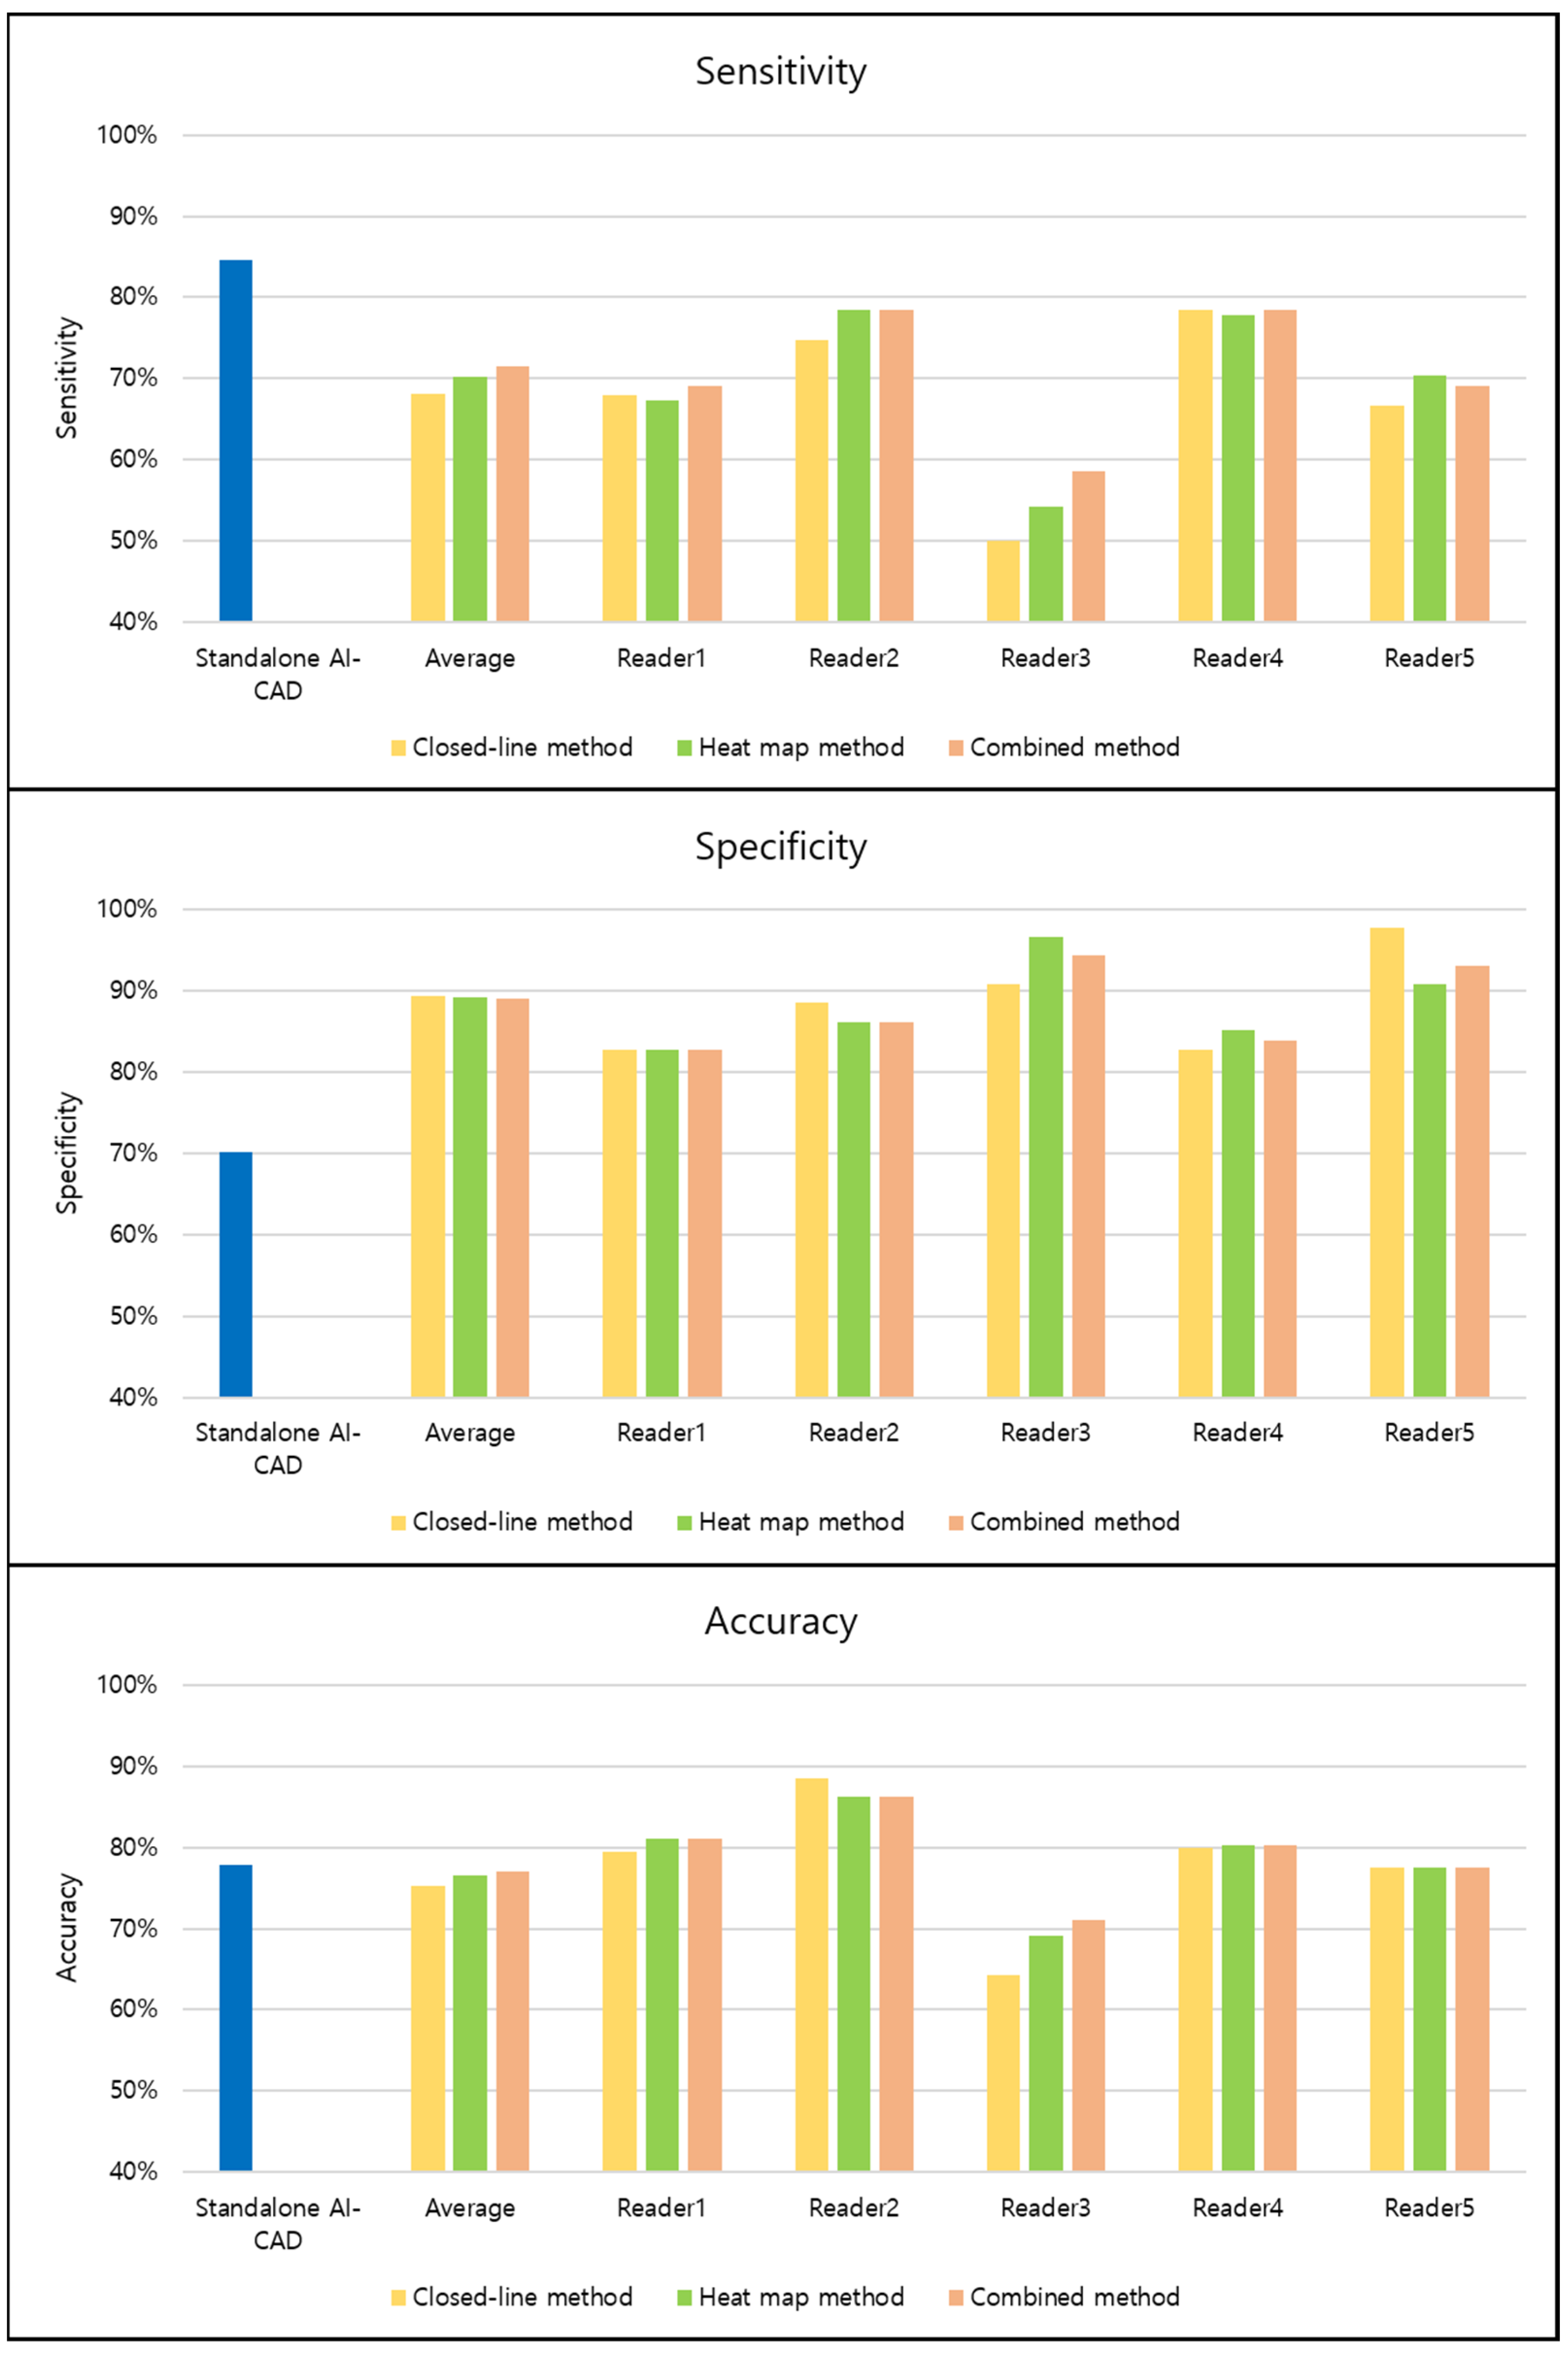

3.4. Variation of Performances across Readers

| Interpretation Method | Sensitivity | Specificity | Accuracy |

| Readers with closed-line method | 68.2% (547/810; 62.2–73.6%) | 89.4% (385/435; 83.6–93.4%) | 75.2% (932/1295; 70.7–79.2%) |

| Readers with heat map method | 70.3% (564/810; 64.3–75.7%) | 89.2% (384/435; 83.0–93.4%) | 76.5% (948/1295; 72.0–80.5%) |

| Readers with combined method | 71.5% (573/810; 65.4–76.8%) | 89.0% (383/435; 83.1–93.0%) | 77.0% (956/1295; 72.6–80.9%) |

| p-value (closed-line vs. heat map method) | 0.129 | 0.884 | 0.224 |

| p-value (closed-line vs. combined method) | 0.007 | 0.745 | 0.037 |

| p-value (heat map vs. combined method) | 0.383 | 0.881 | 0.516 |

| Standalone AI-CAD | 84.6% (137/162; 78.1–89.8%) | 70.1% (61/87; 59.4–79.5%) | 77.8% (198/249; 70.8–83.4%) |

| p-value (vs. readers with closed-line method) | <0.001 | 0.004 | 0.521 |

| p-value (vs. readers with heat map method) | <0.001 | 0.002 | 0.485 |

| p-value (vs. readers with combined method) | <0.001 | 0.003 | 0.492 |